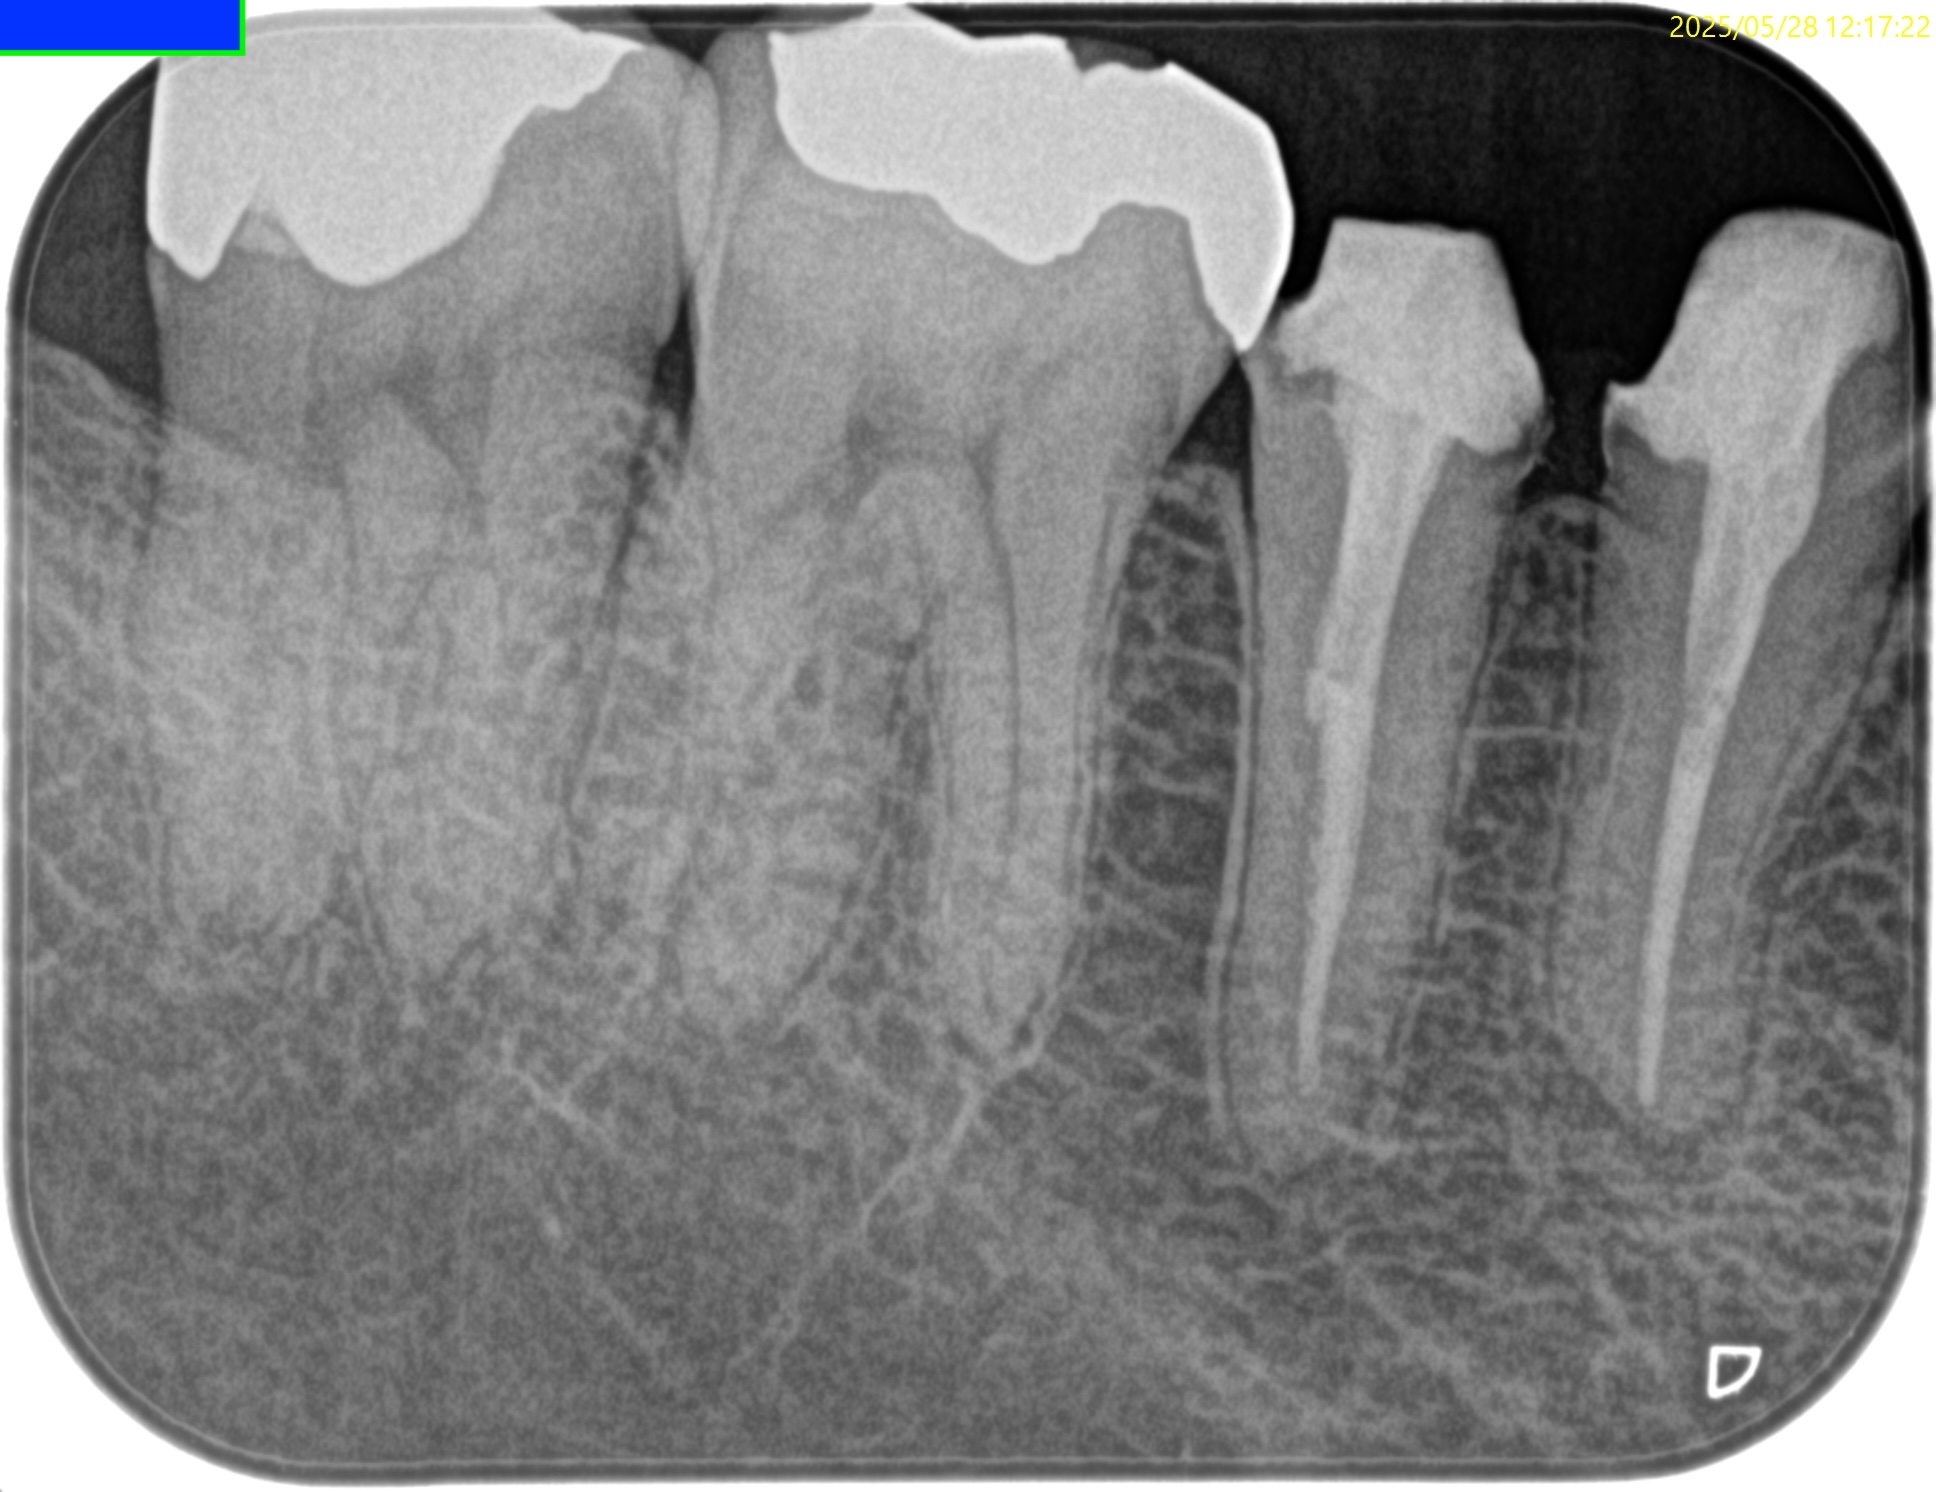

Pre-op Endo test(2026.1.26)

#31 Cold++1/15, Perc.(+), Palp.(-), BT(-), Perio Probe(WNL), Mobility(WNL)

遠心根に直接覆髄的な治療で痛みが出ている。

そして根尖部にはかなり小さいが病変的なものが見える。

Inlayを除去後に根管治療が始まった。

やはり歯髄炎だ。